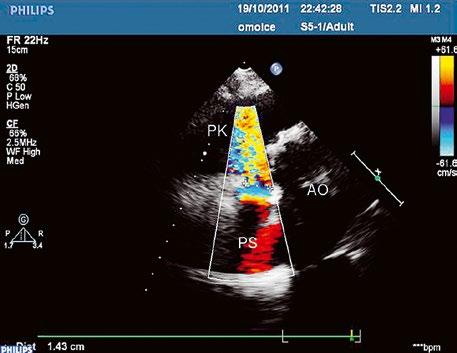

Obr. 45.36 Valvární pulmonální stenóza, doming cípů, jemné cípy, srůst komisur (TEE, longitudinální projekce) AP – kmen plicnice, PK – pravá komora, PS – pravá síň

Obr. 45.37 Valvární stenóza plicnice, jemná chlopeň, doming cípů, TEE, longitudinální projekce, pacient s transpozičním postavením velkých tepen, aorta (AO) je vepředu, plicnice (AP) vzadu